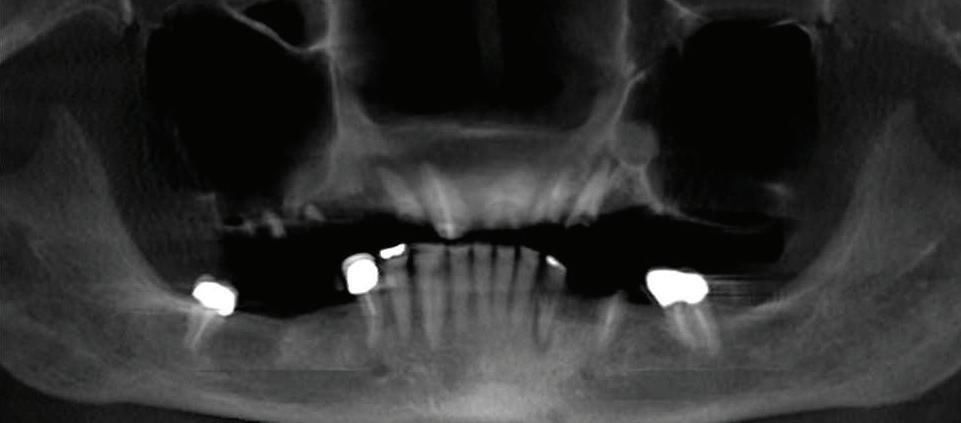

Can just four implants replace all of the teeth on the top or the bottom of your mouth? Thanks to advances in dental implant technology, that answer is a resounding yes.

Believe it or not, tooth loss is extremely common among adults, especially as we age. In fact, more than 35 million people in America are missing all of their upper and/or lower teeth. Rather than living with the discomfort and hassles of dentures, many people are opting for what is called “all-onfour” dental implant restoration.

All-On-Four: One Full Arch Of Teeth, Four Dental Implants

A Reason To Smile Again

able technique for replacing teeth, you should first understand what a dental implant is. An implant is a small titanium screw that fits inside your jawbone and replaces the root-part of a missing tooth. Minor surgery is required to insert the implants. Once the implant is in place, a crown is attached to give you a highly realistic-looking and functional prosthetic tooth.

Here’s where it gets really interesting: You do not need a dental implant for each and every one of your missing teeth. All you need is four precisely placed implants on the top of your mouth, and four on the bottom, to restore your full smile. That’s the beauty of the all-on-four. And because the implant is made of titanium, it has the unique ability to fuse to living bone and function as part of it. So eventually, the dental implant becomes part of the jawbone and serves as a strong, long-lasting foundation for your new teeth.

Besides ensuring that your implants are permanently fixed in place,

Missing Teeth or Tired of Wearing Dentures?

Thanks to advances in dental implant technology, just four implants can replace all of the teeth on the top or the bottom of your mouth.

this bone fusion has another important benefit: it prevents future bone loss in the jaw. This helps to maintain a more youthful facial structure – and better oral health. But perhaps the biggest surprise about the all-on-four is how quickly it can transform your life.

What’s The All-On-Four Dental Implant Procedure Like?

It can be scary to get implants for the first time. Most of that fear is probably due to the uncertainty, so here is the step-by-step process for getting an All-On-Four dental implant.

First, your dentist will want to make sure your comfortable, so either local or general anesthesia will be administered.

Second, the dentist or surgeon will prepare your mouth for the implants, which involves removing your remaining teeth that are failing. They will then remove any diseased or infected tissue from your jaw and gums.

Next, they will begin the implantation process. This means they will

insert the titanium screws into your jawbone. Most likely, they will place two implants toward the front of your mouth and two towards the back of your mouth so the “anchors” can evenly bare the force of the denture.

After the implants have been placed, they will thoroughly clean the surgical sites and suturing all the incisions. Then you’ll be taken to a recovery room where you can relax and take time to wake up from the anesthesia.

How Do You Know If The All-On-Four Procedure Is The Right Option For You?

At your All-On-Four consultation, you’ll receive a 3D CT Scan. This scan will help determine if you need implants and assist your doctors in creating your treatment plan. So if you want to learn more about dental implants, simply schedule a consultation with an All-On-Four provider. It’s the best way to find out how dental implants can change your life.